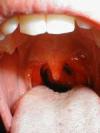

Если ребенок жалуется на плохое самочувствие, первое, что делает большинство родителей - смотрят горло и очень часто обнаруживают, что оно красное. В чем причины и как лечить красное горло мы расскажем в нашей статье.